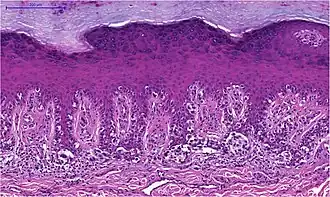

Superfiziell spreitendes Melanom

Das superfiziell spreitende Melanom entsteht in bedeckter, üblicherweise nicht dem Sonnenlicht ausgesetzter Haut. Vorausgegangene Sonnenbrände in der Kindheit und wiederholte Sonnenlichteinstrahlung im Erwachsenenalter sind dennoch ursächlich bedeutsam. Der Tumor wächst überwiegend horizontal zunächst als auf die Epidermis beschränktes Melanoma in situ. Die epidermale Komponente ist zumeist breit und unscharf begrenzt, aber auch scharf begrenzte Läsionen bei klinisch unregelmäßiger Kontur kommen vor.

Die Melanozyten haben große Zellkerne, die häufig auch vergrößerte Nukleolen aufweisen. Mitosen sind in der epidermalen Komponente selten. Das Zytoplasma ist üblicherweise weit und der Pigmentgehalt kann innerhalb einer Läsion stark wechseln. Die Tumorzellen breiten sich einzeln oder in unregelmäßigen, teils miteinander verbundenen Nestern in der Epidermis aus und folgen dabei Adnexstrukturen. Typisch für das superfiziell spreitende Melanom ist das als pagetoid bezeichnete Wachstumsmuster: atypische Melanozyten finden sich nicht nur entlang der Junktionszone, sondern verteilt über die ganze Breite der Epidermis bis in oberflächliche Zelllagen.

Die dermale Komponente superfiziell spreitender Melanome ist in der Regel asymmetrisch aufgebaut. Eine Ausreifung der Melanozyten fehlt und es finden sich Mitosen. Selten zeigen sich nekrotische (abgestorbene) Melanozyten. An der Basis des Tumors und eventuell auch zwischen den Tumorzellen besteht ein hauptsächlich lymphozytäres Entzündungsinfiltrat.[44]